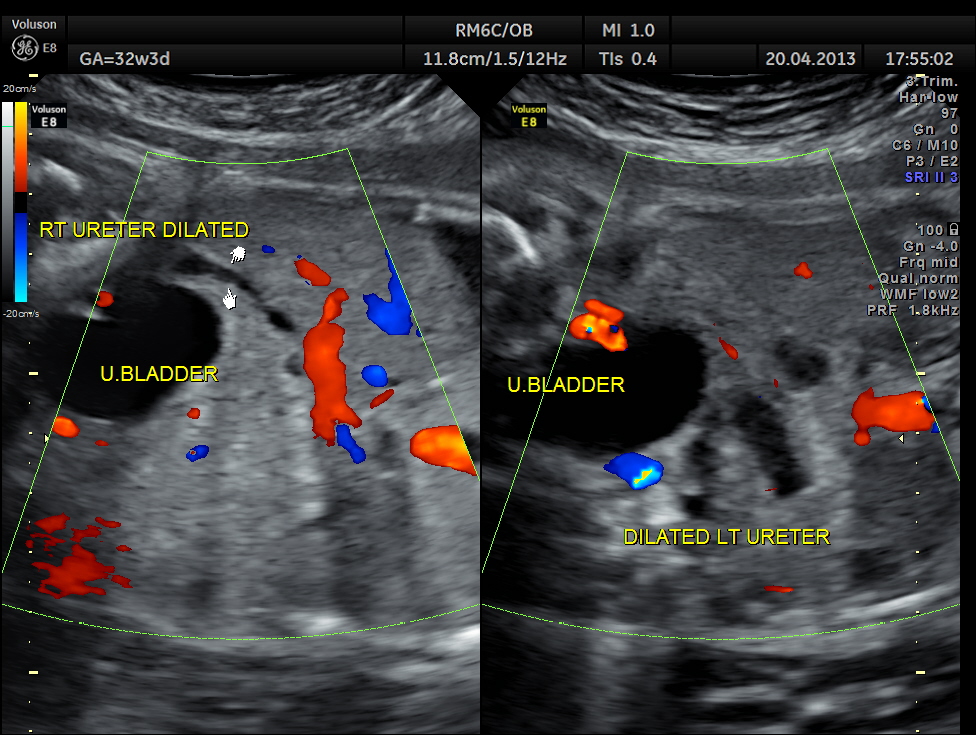

The following images show bilateral renal pelvi ectasis and bilateral dilated ureters with all the changes more in the left kidney .

The left kidney also showed possible duple-ix pelvis with double ureters arising from them . But this finding could not be confirmed in all the views .